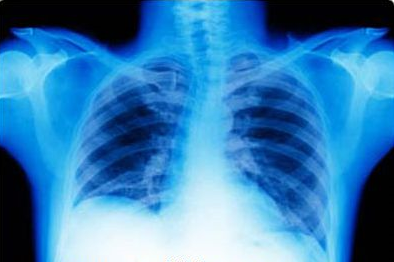

有一位病人自诉三个月前由感冒引起咳嗽气喘,吃了好多治感冒的成药,西药用抗病毒的,抗细菌的,都不起作用。后到济南省立医院找专家诊治通过各种化验,CT扫描,诊断为肺炎进行输液治疗。治疗了半个月也不见好转。最后做了气管镜取出肺部一些组织通过化验才明确诊断.定为肺癌(腺癌)要求患者手术治疗。患者拒绝手术,寻求中医治疗。于是患者就找到李聪明要求给治疗。

舌红苦黄腻,脉浮滑数。诊断:肺不宣降,痰热阻肺,方药:炙麻黄10g,白果10g(打)黄芩10g,杏仁10g,大贝10g,瓜萎30g,芦根 30g,元参30g,牡蛎30g,三棱10g.莪木10g,半夏10g。陈皮 10g,茯苓30g,银花15g,半枝莲30g,铁树叶30g,白花蛇舌草 60g。甘草6g。7付水煎服。每次来诊都以此方为基础。辨证加减。一年半后病情有好转,有做了一个cT扫苗病罩好转。继续用中医中药治疗。此病人是因感冒后心情不太舒畅到致气血郁滞邪结于肺。 肺气不得宣降故咳嗽气喘邪结于肺郁而化热,故咳吐黄痰,肺脏气滞血瘀,痰瘀互阻形肺部中,下叶结块。故cT扫苗发现病罩。肺癌中医叫肺结或肺痿。本例患者属肺结。